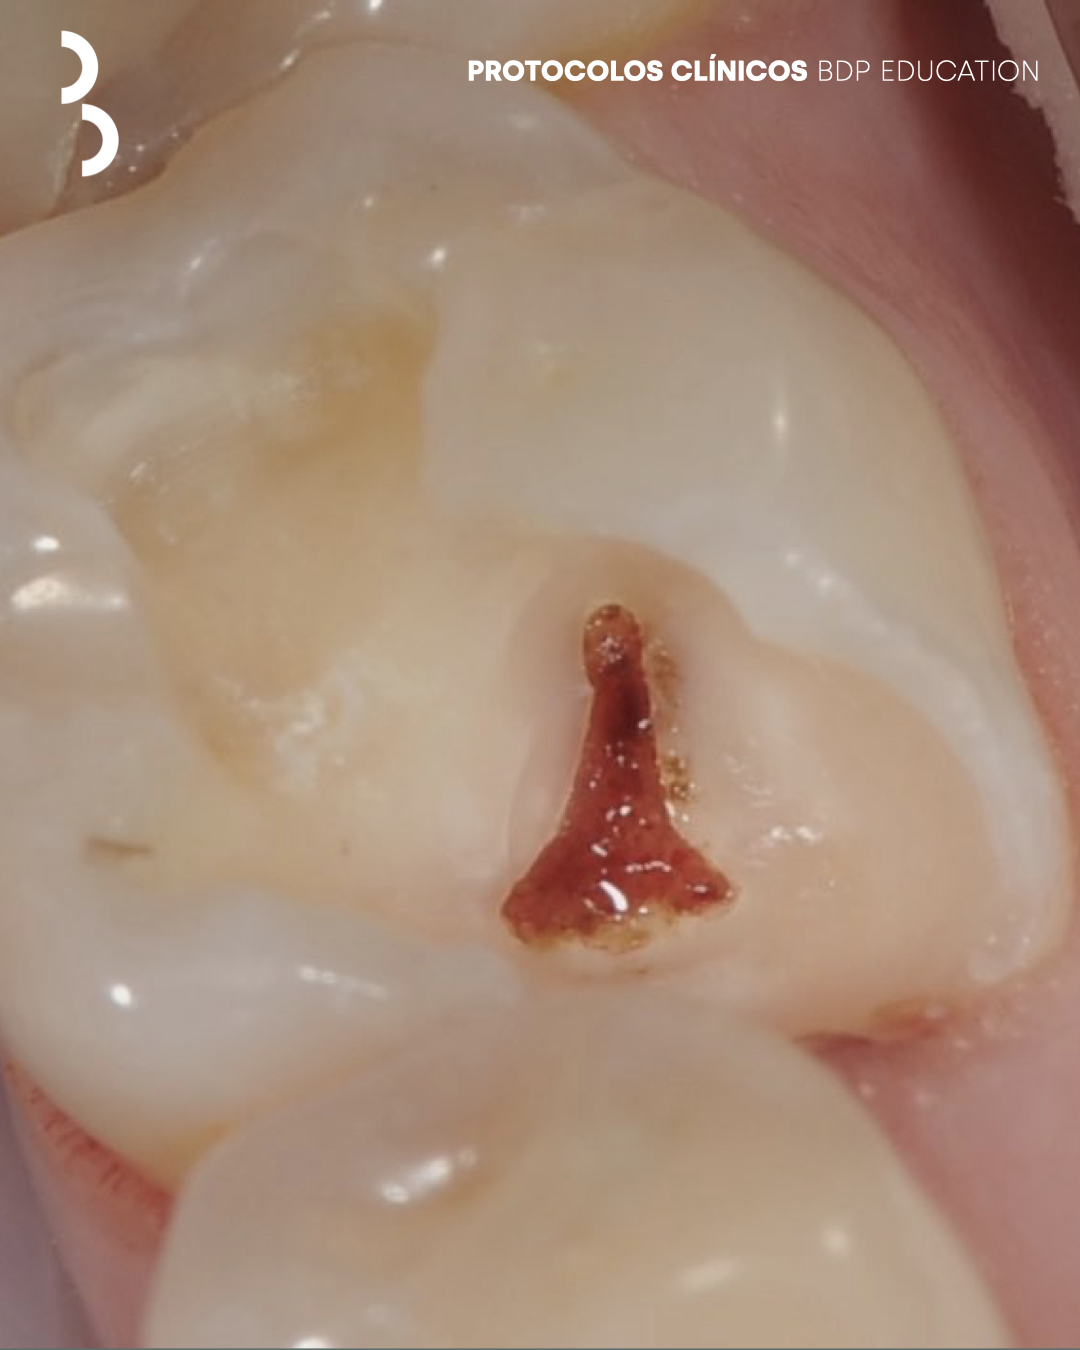

A terapia pulpar vital tem como objectivo a preservação da vitalidade pulpar em dentes com inflamação reversível, promovendo a manutenção da função biológica do órgão pulpar e evitando tratamentos mais invasivos. A sua previsibilidade depende de um diagnóstico preciso, de um controlo rigoroso do campo operatório e da correta selecção dos materiais e técnicas.

Este protocolo clínico estabelece uma abordagem estruturada para a realização da terapia pulpar vital, incluindo a avaliação clínica e radiográfica, os critérios de indicação e contraindicação, o controlo da hemorragia e a proteção adequada do complexo dentino-pulpar.

O documento enfatiza a importância do isolamento eficaz, da remoção seletiva de tecido cariado e da utilização de biomateriais, com o objectivo de favorecer a cicatrização pulpar e a formação de dentina reparadora. A abordagem é orientada por princípios biomiméticos, privilegiando a preservação máxima da estrutura dentária e da biologia pulpar.